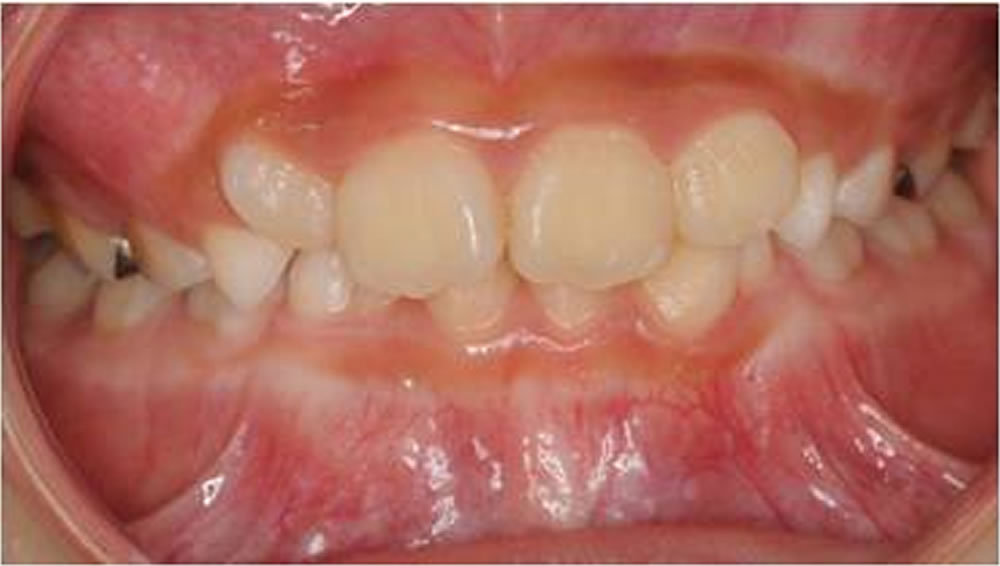

BiVi歯科・矯正歯科で実施した小児矯正の治療例をご紹介

▼当院で実際に行った小児矯正治療の症例をご紹介します。